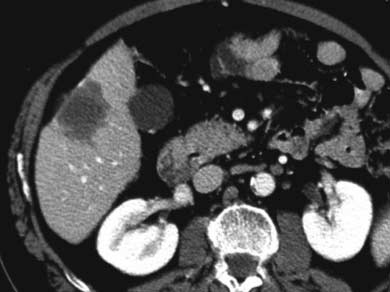

ก่อนทำ

RFA |

หลังทำ